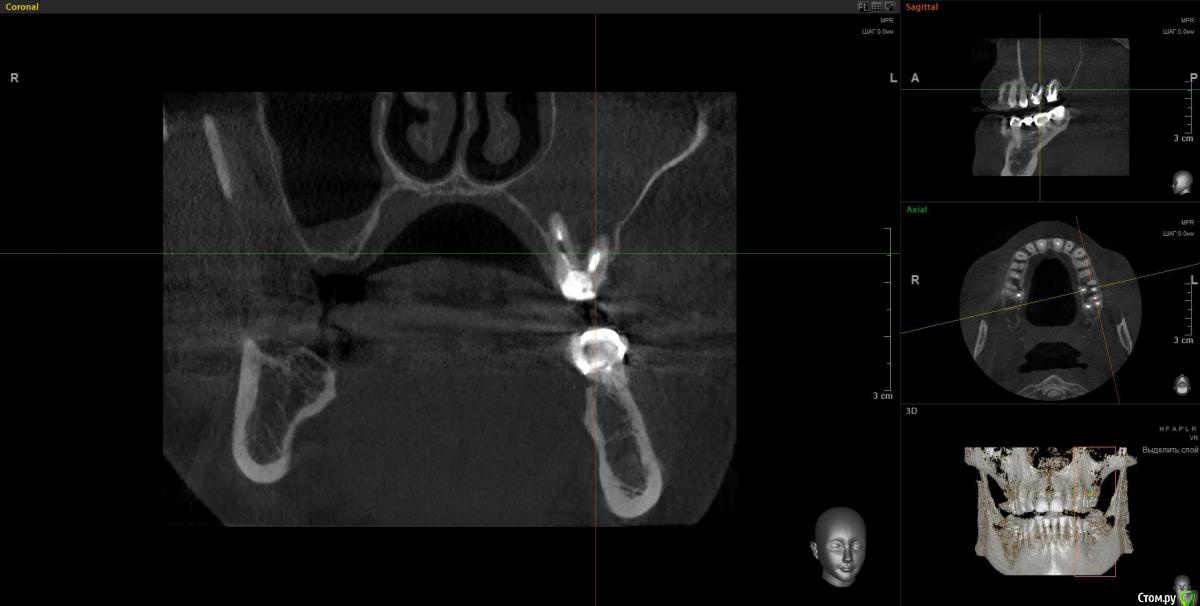

Doctor Vlad Опубликовано 14 апреля, 2020 Автор Поделиться Опубликовано 14 апреля, 2020 А дальнейшие планы каковы? Просто санация либо планируется реконструкция?Очень в тему вопрос. На работе задумался- а что дальше? и проблемка стала шире... как раз кт скинули. Там же не просто зашить и забыть там 2 импланта нужны)Кт до удаления месяца 2 назад. Стрелочка место где виднелась слизистая пазухи в момент удаления. по моим расчетам можно было бы без синуса если вся полость кисты заполнится костью, но теперь там будет скорей всего тяж или клапан этот. киста сама дно синуса приподняла. Ссылка на комментарий

Doctor Vlad Опубликовано 14 апреля, 2020 Автор Поделиться Опубликовано 14 апреля, 2020 Снимок до Ссылка на комментарий